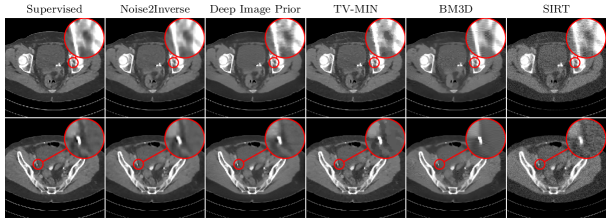

Refer to caption

Figure 6: Results of supervised training, Noise2Inverse, Deep Image Prior, TV-MIN, BM3D, and SIRT on Low-dose CT grand challenge data with simulated noise. The red insets display the algorithm output.

We compare the same methods as before. The dataset was split into a training dataset, consisting of nine patients, and a test set, containing the remaining patient. Both Noise2Inverse and the supervised CNN were trained on the training set. The optimal hyperparameters for SIRT, TV-MIN, and BM3D were determined on the training set. The Deep Image Prior, including its hyperparameters, was directly optimized with respect to the slices displayed in Figure 6. Metrics were calculated on the full volume of the test patient, and on the top displayed slice in Figure 6.

Results are shown in Figure 6 and Table II. The Noise2Inverse method achieves similar results to TV-MIN, but without the staircasing artifacts. The difference between the methods is smaller in this experiment. For the SSIM metric, this is likely due to the low contrast of structures of interest compared to the full intensity range of the reconstructions. In general, compared to previous experiments, the noise has significantly lower intensity, and many different objects structures are present, each of which must be learned by the neural network.